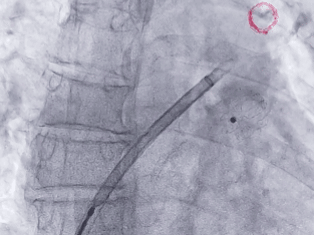

术中DSA肝位造影并测量心耳大小:菜花型左心耳

开口24.3mm,深度24.7mm

该心耳为菜花型,此类心耳一般多为囊袋状多分叶,术前造影评估远端梳状肌较为发达,开口24.3mm,深度24.7mm,深度足够,建议选择LAFDQ-26封堵器进行封堵。

封堵器展开后造影

封堵器完全展开,封堵器未露肩

封堵器稳定封堵,无残余分流

压缩比10.95%

Lefort封堵器评估符合PASS原则,释放封堵器,封堵器位置稳定且未见残余漏

术前结合CT以及术中造影评估左心耳开口24.3mm,深度24.7mm,术中考虑心耳开口和深度充足,可利用心耳空间进行退鞘释放封堵器,使封堵器完全封堵左心耳。术中调整封堵器在心耳内的位置形态,确保封堵器放置位置合适,且牵拉稳固,术后封堵器形态完整,未见残余漏。本病例展开后即刻造影,平口封堵,上下缘不留残腔。封堵器压缩比为10%,压缩合适,术中符合PASS原则,释放封堵器,术后封堵器稳固锚定在心耳壁,封堵器与心耳紧密贴合,无过度扩张风险,显著提升封堵完整性。